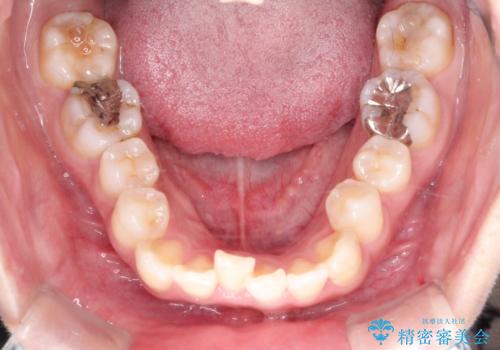

- 主訴:口元を下げて前突感を無くしたい、下の歯の凹凸も無くしたい

右側第二小臼歯、左側第一小臼歯、下顎両側第一大臼歯を抜歯しワイヤ-矯正を行いました。

骨格的顎の変位を認めたため、顔貌に対しピッタリ上下の歯の正中を合わせることは難しいと説明し、上下左右計4本小臼歯を抜歯しワイヤー矯正治療を行いました。